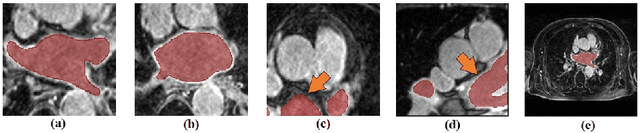

Abstract:Left atrial (LA) segmentation is a crucial technique for irregular heartbeat (i.e., atrial fibrillation) diagnosis. Most current methods for LA segmentation strictly assume that the input data is acquired using object-oriented center cropping, while this assumption may not always hold in practice due to the high cost of manual object annotation. Random cropping is a straightforward data pre-processing approach. However, it 1) introduces significant irregularities and incompleteness in the input data and 2) disrupts the coherence and continuity of object boundary regions. To tackle these issues, we propose a novel Dynamic Position transformation and Boundary refinement Network (DPBNet). The core idea is to dynamically adjust the relative position of irregular targets to construct their contextual relationships and prioritize difficult boundary pixels to enhance foreground-background distinction. Specifically, we design a shuffle-then-reorder attention module to adjust the position of disrupted objects in the latent space using dynamic generation ratios, such that the vital dependencies among these random cropping targets could be well captured and preserved. Moreover, to improve the accuracy of boundary localization, we introduce a dual fine-grained boundary loss with scenario-adaptive weights to handle the ambiguity of the dual boundary at a fine-grained level, promoting the clarity and continuity of the obtained results. Extensive experimental results on benchmark dataset have demonstrated that DPBNet consistently outperforms existing state-of-the-art methods.